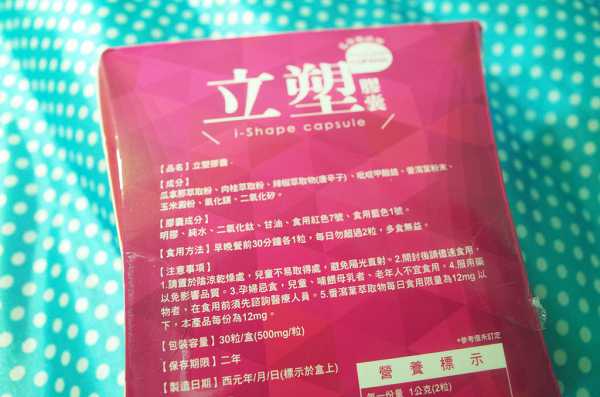

Supercut塑魔纖立塑膠囊的成分有:瓜拿那萃取粉、肉桂萃取粉、辣椒萃取物(唐辛子)、吡啶甲酸鉻、番瀉葉粉末、玉米澱粉、氧化鎂、二氧化矽。

之前上過相關課程,成分表是依照每項成分的多寡來排列順序,排在最前面的就是產品的主要成分!

食用方式:早晚餐前30分鐘各1粒,每日不超過2粒。(多食無益)

番瀉葉萃取物每日食用限量為12mg以下,

番瀉葉萃取物每日食用限量為12mg以下,